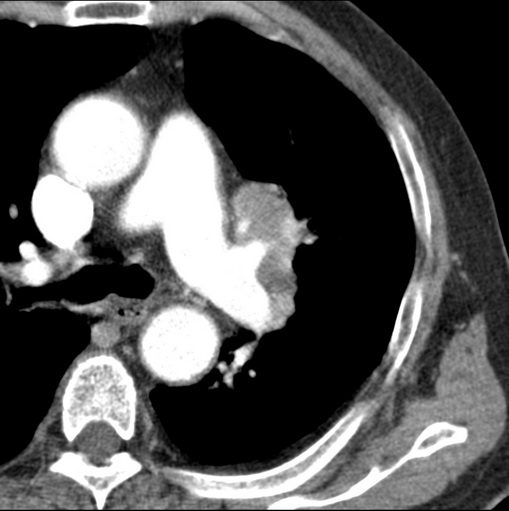

肿块贴近左肺门,包绕左上肺动脉,形态不规则。肿块增强扫描中度强化。纵膈内主动脉弓左旁间隙、气管隆突前、下间隙见多枚淋巴结影。综上考虑左侧中央型肺癌可能性大。图片没有完整上传,尤其是左肺上叶支气管分支层面没有上传,因此不好判断是叶支气管中断还是段支气管中断。另外,下图红色部分所示是“黏液支气管征”吗?

强化较典型,左上肺癌并纵膈淋巴结转移;左上肺结核并空洞形成;胸膜增厚.